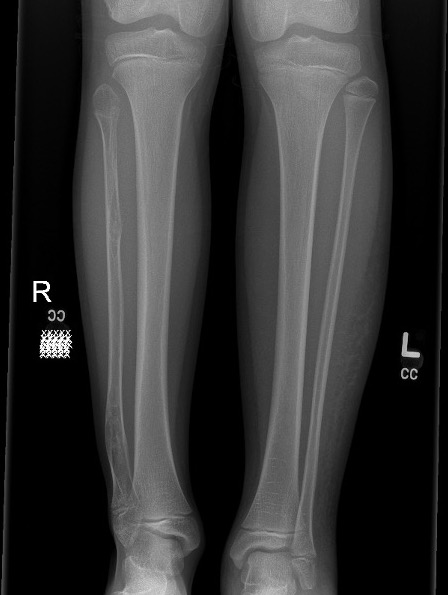

Location

Femur / tibia / humerus

Growth disturbance

- leg length discrepancy

- bowing